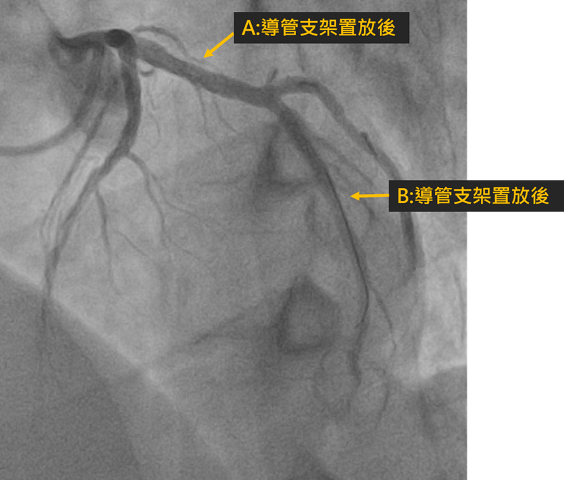

本院健檢中心成功偵測無症狀的嚴重冠狀動脈狹窄問題黃成偉醫師另外分享43歲林先生的案例,林先生任職於南科某高科技公司,至安南醫院健檢時,發現其冠狀動脈血管鈣化。雖然他自述平常無明顯症狀,且無高風險病史,但黃成偉醫師仍建議安排1024切電腦斷層,這才發現心臟冠狀動脈有多處嚴重狹窄;所幸,後續透過心導管支架置放,成功打通嚴重狹窄的血管,免於未來心臟病發作的風險。